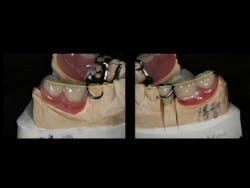

In addition, the correct length of the central incisor was calculated by using the ideal length-to-width ratio tool found in the Dawson Wizard Software (figure 15). As a result, this change could be transferred to the mounted models (figures 16 and 17). This new vertical and horizontal position of the central incisor provided a guide for the upper occlusal plane. Once the upper occlusal plane was established, re-creating the lower plan became more simplified.

In this case, the diagnostic wax-up of the mounted models gave the technician the new position of the upper incisal edge. The technician then set the maxillary teeth appropriately using models and additional photographs. At the same time, tooth No. 20 was restored, but the lab technician kept the crown and lower partial to predictably create the lower occlusal plane and easily articulate this with the upper immediate denture (figure 18). Note the improved curve of Spee in Figures 19 and 20. Upon completion of the prosthesis, treatment was completed as outlined and the results made the patient feel very comfortable functionally, esthetically, and phonetically.